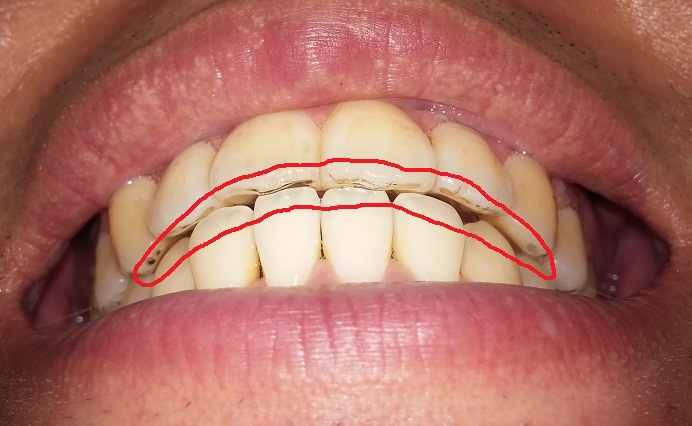

현재 이 부분(빨간부분)이 병원과 저와의 만족선? 합의점?이라고 해야 될까요?

일단 치아배열은 웬만해서는 중심선에 맞추기 힘든 상악·하악이 일치 되었고

치간 사이도 틈 없어 음식물이 치아 사이로 끼지 않아 잘 마무리 되었다고 생각합니다.

다만, 제 욕심 같아서 송곳니 부분과 앞니 부분이 서로 교합이 되었을 때,

뜨는 부분이 없이 빈 공간을 메우고 싶었으나,

치아교정을 마무리하던 약 3달간일회용 고무줄을 착용했음에도 불구하고 완전히 닫혀지지 않아